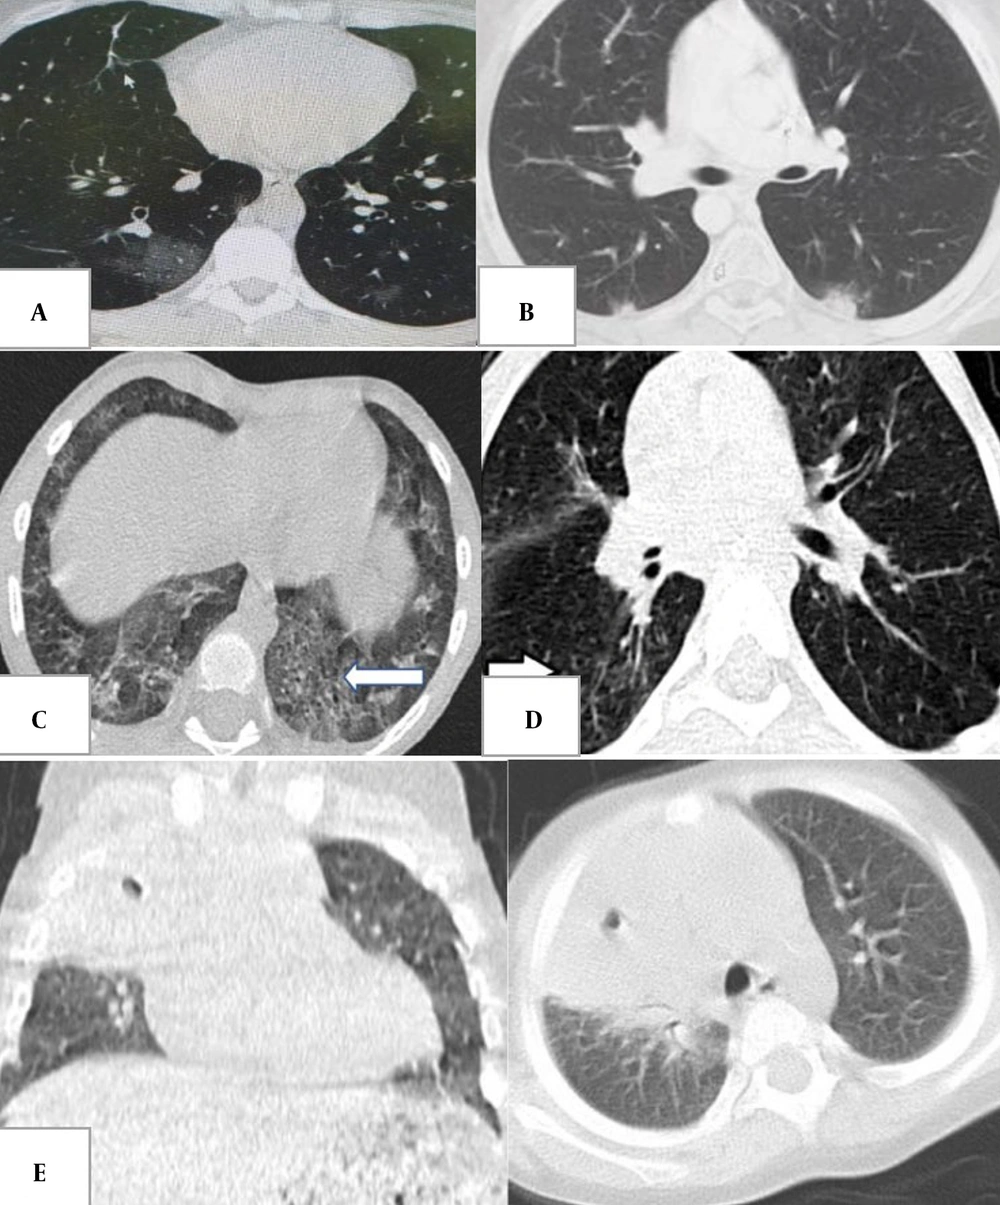

Typical pediatric CT patterns include peripherally located multifocal GGO and consolidation, predominantly in the lower lobes (Figures 1 and 2) (27, 29-35). Peribronchial thickening and tree-in-bud patterns are more common in children than in adults (29, 30, 33). Consolidation with a halo sign is frequent but must be distinguished from fungal infection in immunocompromised patients (29, 33, 35). The crazy paving and reverse halo signs are less common (29, 30, 32). Lobar consolidation without GGO, lymphadenopathy, or significant pleural effusions may indicate alternative diagnoses or bacterial superinfection (31, 32). Pulmonary embolism is rare in children (32, 36).

A, bilateral multifocal peripheral and round ground-glass opacities in a 12-year-old boy with fever and cough, typical for coronavirus disease 2019 (COVID-19); B, halo and reverse halo sign in a 12-year-old boy with a history of bone marrow transplantation and persistent fever (typical for COVID-19); C, crazy paving appearance in the left lower lobe (arrow) in a 6-year-old with fever and respiratory distress (typical for COVID-19); D, tree-in-bud appearance in the right lower lobe (arrow) in a 6-year-old boy (atypical for COVID-19); E, consolidation and cavitation in the right upper lobe in a 2-year-old girl with Gaucher disease and congenital neutropenia with respiratory symptoms (atypical for COVID-19).